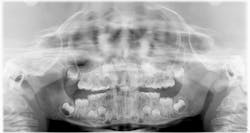

Patient: 7-year-old male

- Radiolucency appeared to focalize around the coronal portion of no. 7

- Ill-defined radiopacity within the osseous tissue under the area where primary tooth D would be located

- Not tender to palpation and no expansion in the vestibular area

- Patient had experienced trauma to the area a few years back while playing

Patient: 6-year-old male

- Tooth no. 9 had erupted normally after exfoliation of tooth F, but tooth E was still present

- Chief concern: Permanent teeth in the areas of nos. 7 and 8 might not be developing.

- Large radiodense area in the region apical to teeth D and E

- Otherwise healthy patient